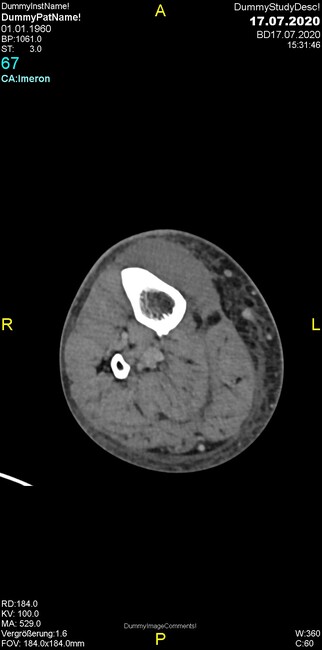

Um welche Modalitäten handelt es sich?

- Röntgen p.a. und lateral, CT coronar Knochenfenster, CT axial Weichgewebsfenster

Was fällt in der Projektionsradiographie auf?

- Verdichtung im Recessus suprapatellaris

- Aufhellungslinie in Projektion auf die Femurkondylen

- Erhöhter tibialer Slope

- Hypertransparenz tibial

- Subluxationsstellung im Kniegelenk

Was trifft auf den Befund zu?

- Der Befund beschränkt sich auf den Knochen.

- Es besteht hochakuter Handlungsbedarf.

- Der Befund ist tendenziell benigne.

- Der Befund ist tendenziell maligne.

- Der Befund weist einen Zusammenhang zum Patientenalter auf.

Was fällt in der CT im Knochenfenster auf?

- Mediale Gelenkspaltverschmälerung

- Dezente Erosion der fibulären Kortikalis

- Frakturspalt der lateralen Tibiametaphyse

- Weichgewebskalzifikationen lateral angrenzend an den Gelenkspalt

- Osteolyse der Tibiametaphyse unter Beteiligung der Kortikalis

Was kommt differentialdiagnostisch in Frage?

- Kompartmentsyndrom

- Osteomyelitis mit Weichgewebsanteil

- Metastase mit pathologischer Fraktur

- Rheumatoide Athritis

- Posttraumatische Verletzung